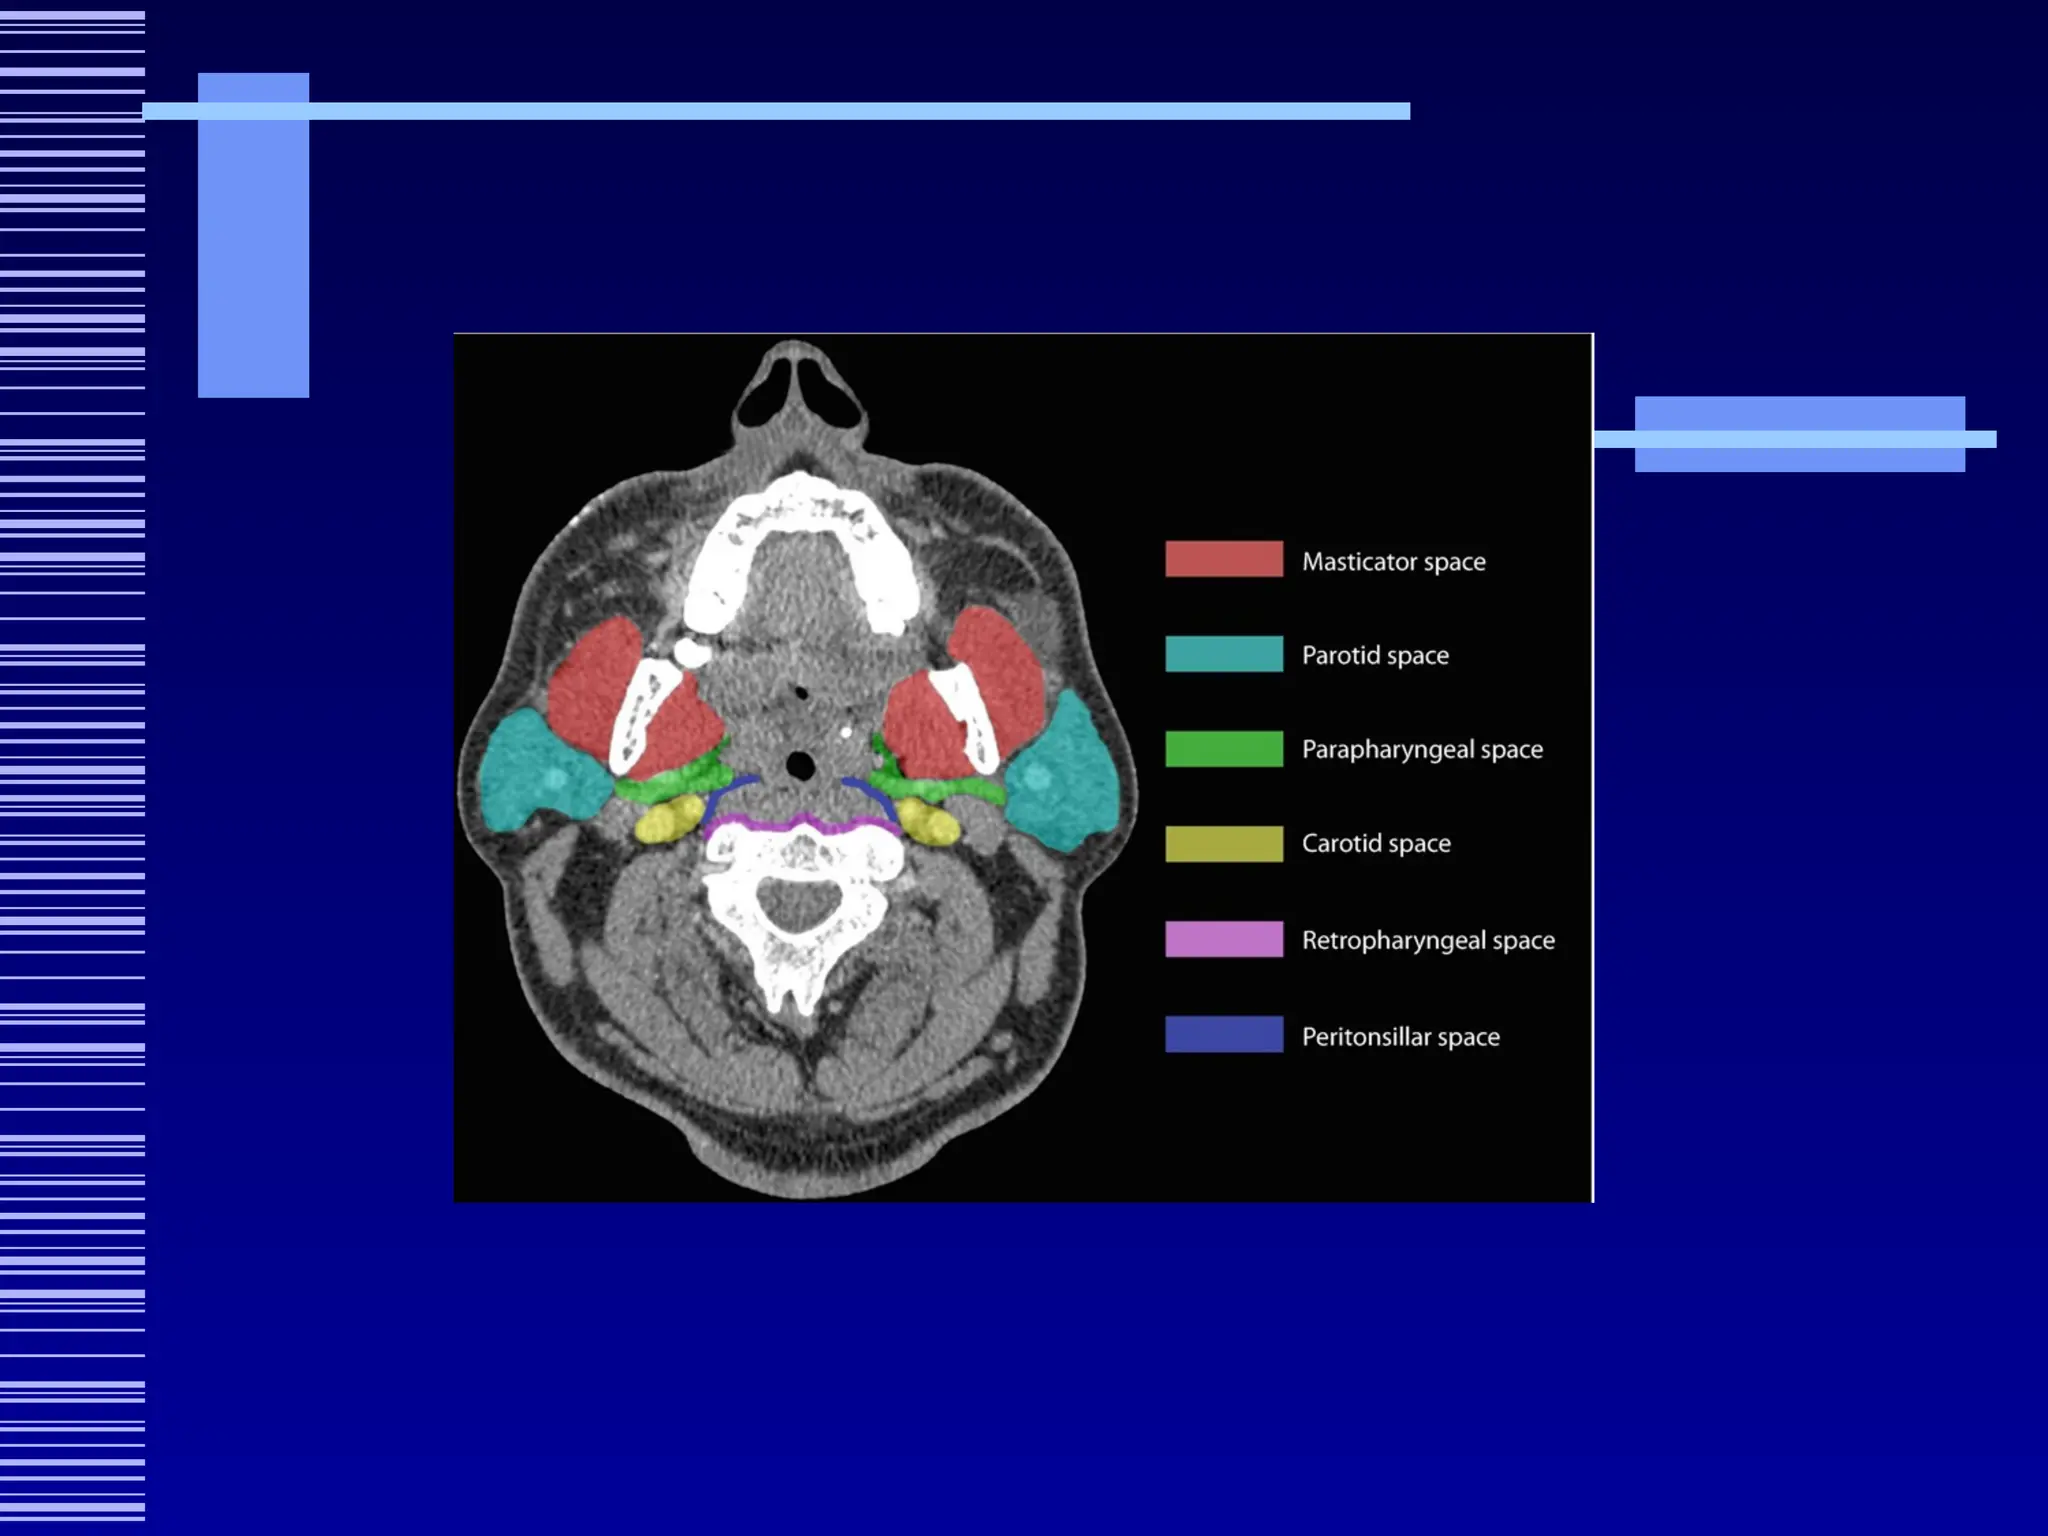

Suprahyoid Deep Neck Spaces

 Sublingual Space

 Submandibular Space

 Peritonsillar Space

 Parapharyngeal Space

 Pharyngeal Mucosa Space

 Masticator Space

 Parotid Space